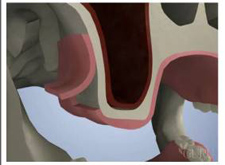

上顎骨の内部には上顎洞と呼ばれる大きな空洞が存在します。

歯がなくなると、歯槽骨の吸収が進行します。

上顎の場含は、図のように上顎洞の拡大も進行する可能性もあり、歯槽骨はさらに薄くなります。

歯槽骨の骨量が少なくなると、インプラントが埋入できなくなリます。